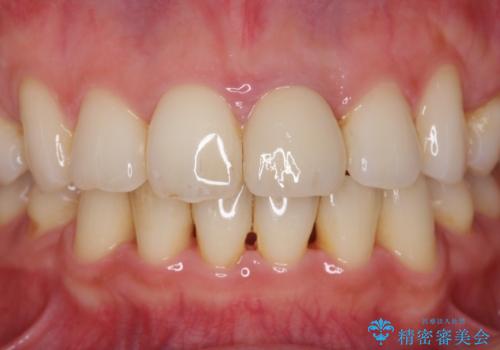

変色してきた前歯をセラミック治療

- 神経の治療をしたまま放置していた歯が、変色してきたので改善したい。と前歯の審美性の改善を求めて来院されました。

根管治療後の歯には部分的な修復処置が為され、変色が進行している状態でした。

ジルコニアクラウンを用いて、自然な色調となるよう治療を計画します。

根管治療は行わず、仮歯・ジルコニアクラウンのみの処置を行い自然な歯に仕上げることができました。